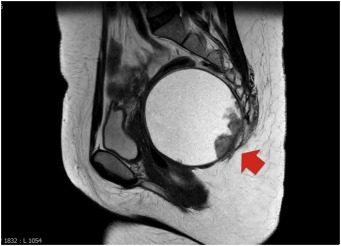

Sometimes they are diagnosed during routine examination but mostly the majority of the patients show symptoms of tailgut cyst. This condition is often misdiagnosed, so MRI is considered a modality of choice to get clear images.

Colonoscopy is helpful if the patient presents with the symptoms of rectal bleeding. Moreover, the integrity of the layers of the rectum can be visually seen through transrectal ultrasound. But the multiplanar imaging ability of MRI aids in identifying the cyst rapidly.

However, the pathogenesis of malignant tailgut cancer is not crystal clear. There are chances that malignant tumor cells might leak during a biopsy in the peritoneal cavity which would lead to cancer. So, the vital diagnosis tools are CT scans and MRI.